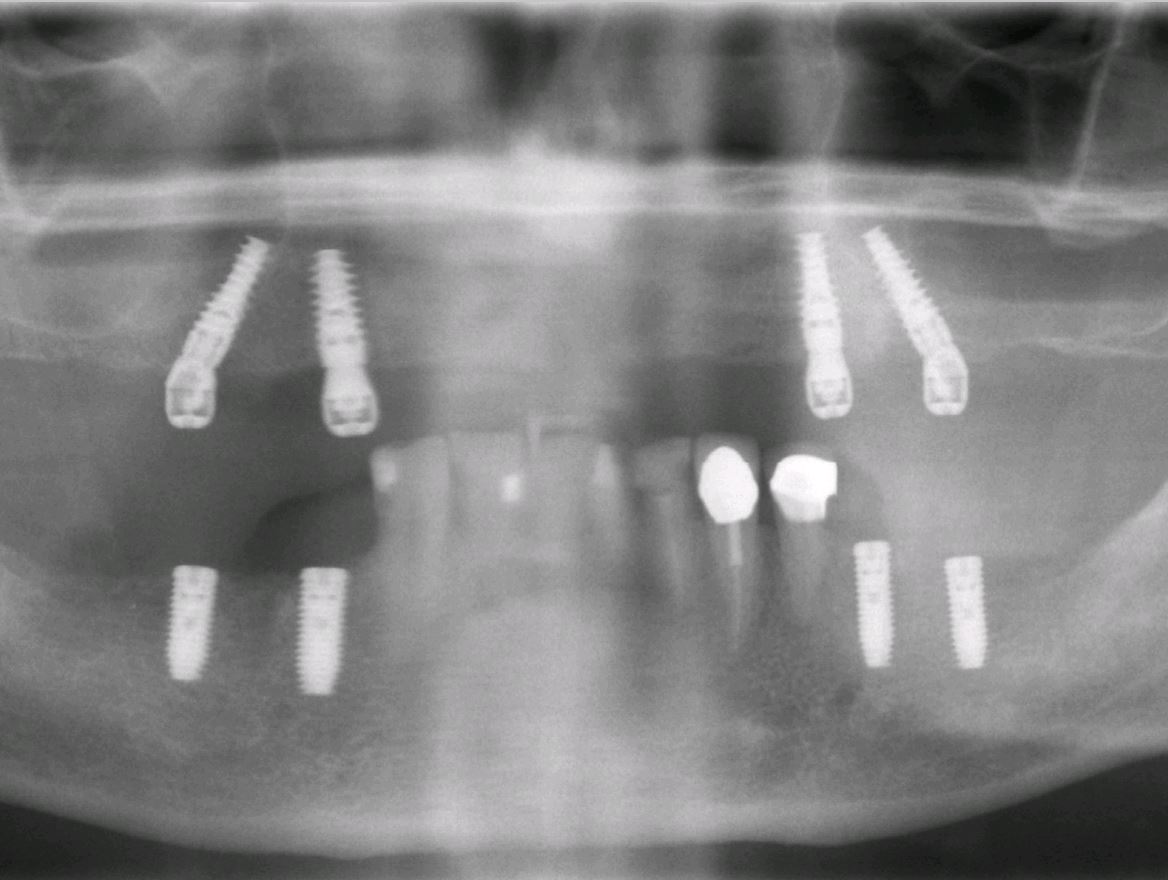

Sind nun alle Zähne des Kiefers verloren gegangen oder ist es notwendig alle restlichen Zähne zu entfernen, bleibt den Patienten normalerweise nichts anderes als eine konventionelle Vollprothese. Hier kann durch das spezielle Verfahren des Einbrigens von vier Implantaten ein Zahnersatz bereits in sehr zügiger Weise im Mund befestigt werden. Diese Methode ist an bestimmte Vorgaben gebunden und nicht immer ohne weiteres anwendbar. Bei günstigen Bedingungen kann es sogar möglich sein sogenannte "feste Zähne an einem Tag" zu bekommen.

All-on-4-Behandlungskonzept